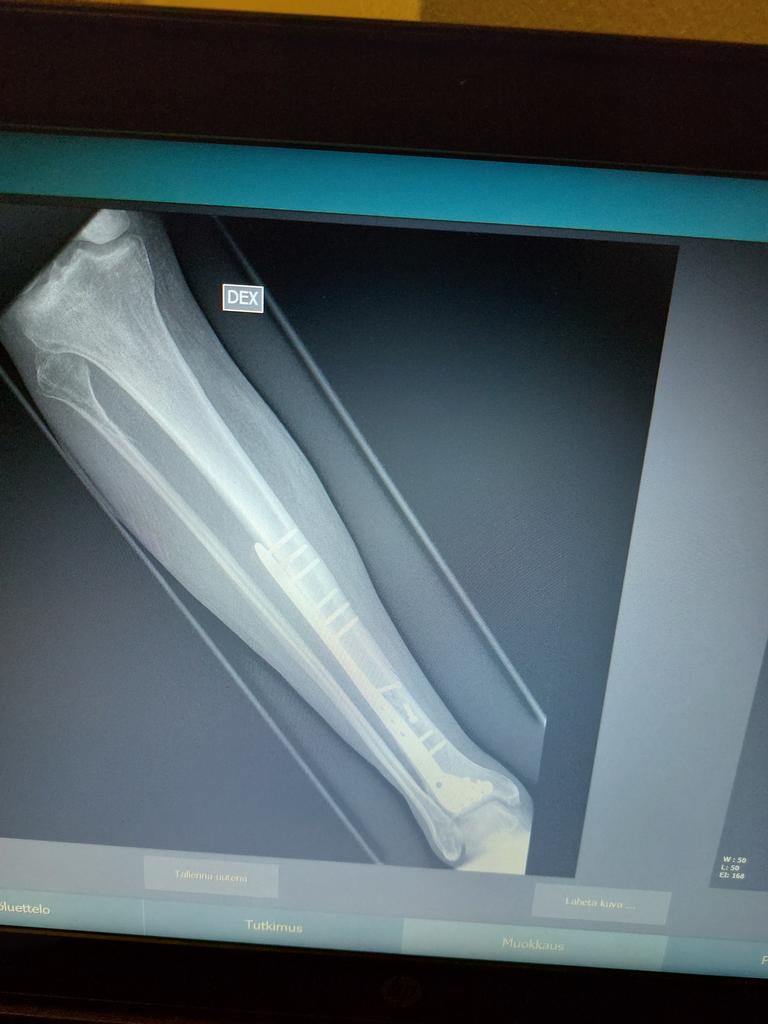

Aloitan jalkani telomisesta....

Poikki on ja eiku leikkaukseen...

Rautaa ja ruuveja on kuin pienessä rautakaupassa...

Oma valinta sekin toki on, mutta sanoisin, että kannattaisi editoida pois. Komeasti on vahviketta laitettu jalkaan.